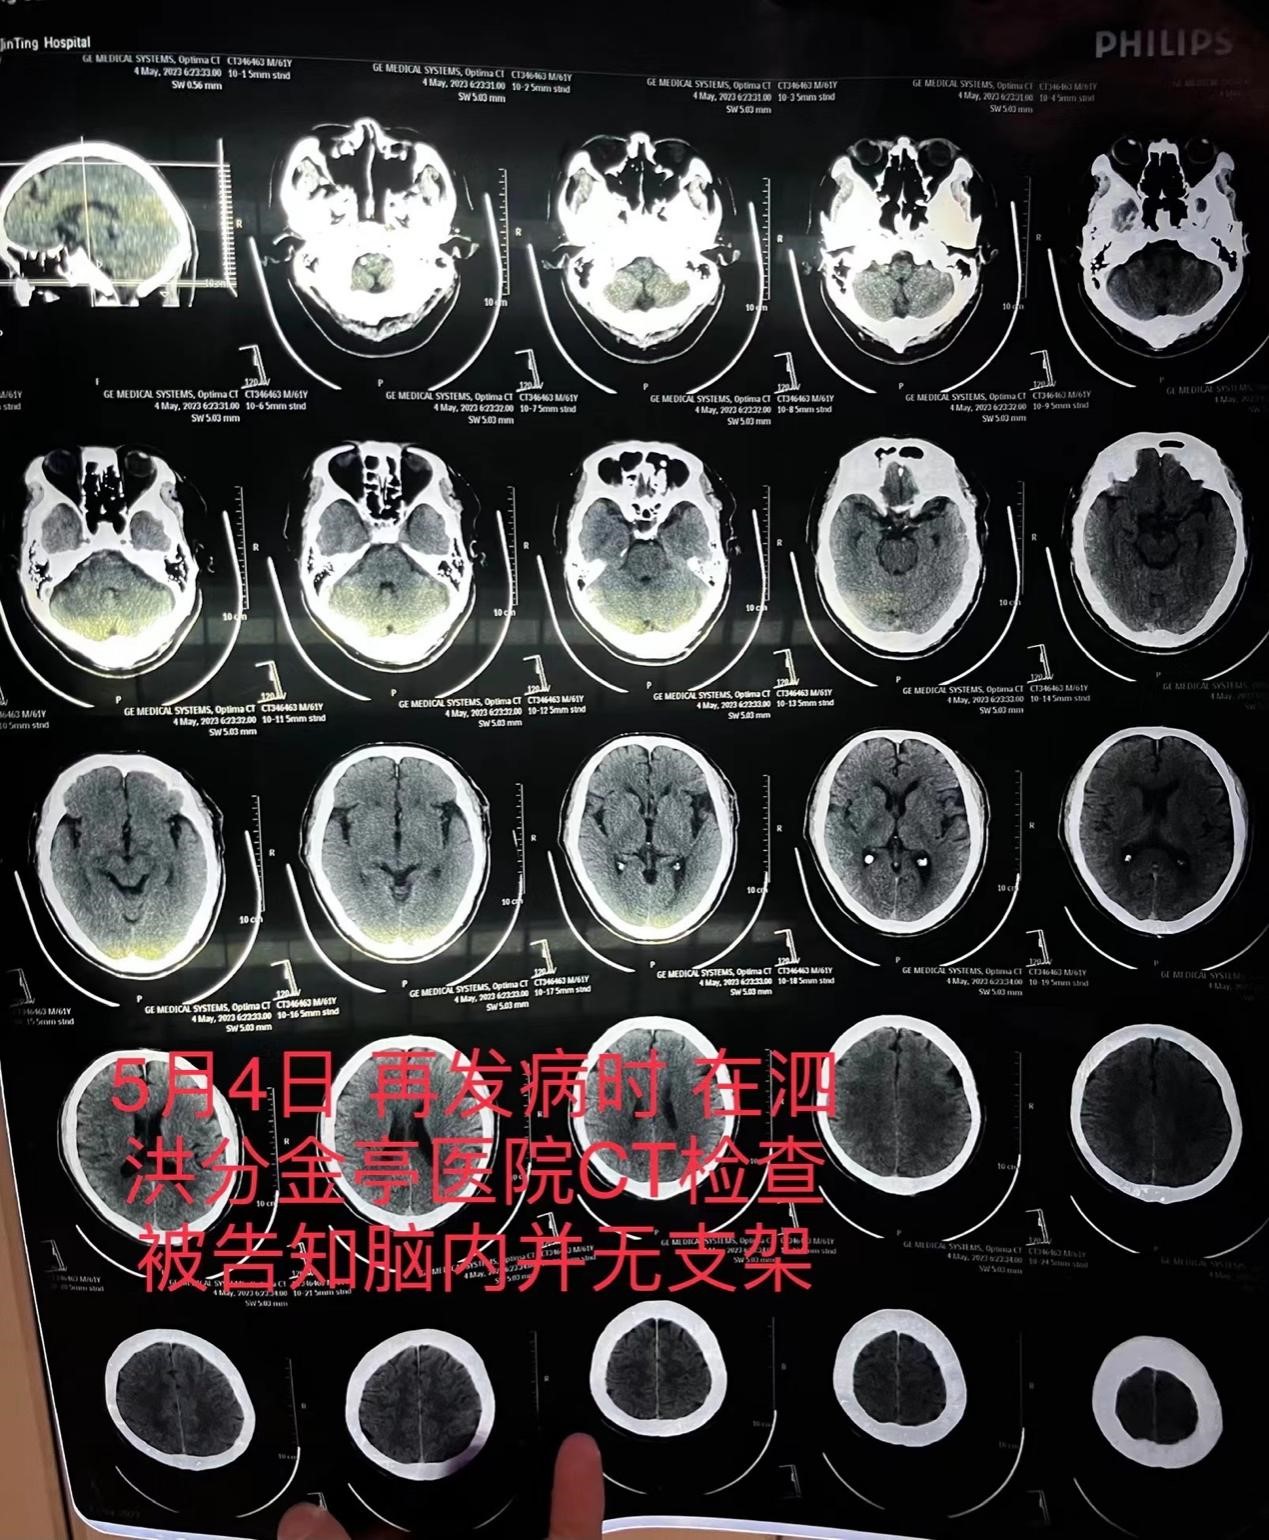

朱老汉在泗洪县分金亭医院的CT检查报告,显示颅内并无支架。朱先生 供图

4月10日,朱老汉出院,病情稳定好转,住院医疗费用合计12万余元,部分自费。但还不到一个月,5月4日,朱老汉突发严重脑梗,被送至江苏省宿迁市泗洪县分金亭医院抢救。该院的CT血管造影显示,其颅内段部分动脉已严重堵闭,同时,并未发现植有支架。朱老汉随后被家人转入宿迁市第一人民医院,曾作为主刀医生的齐某此时承认,之前未能在患者颅内血管成功植入支架。